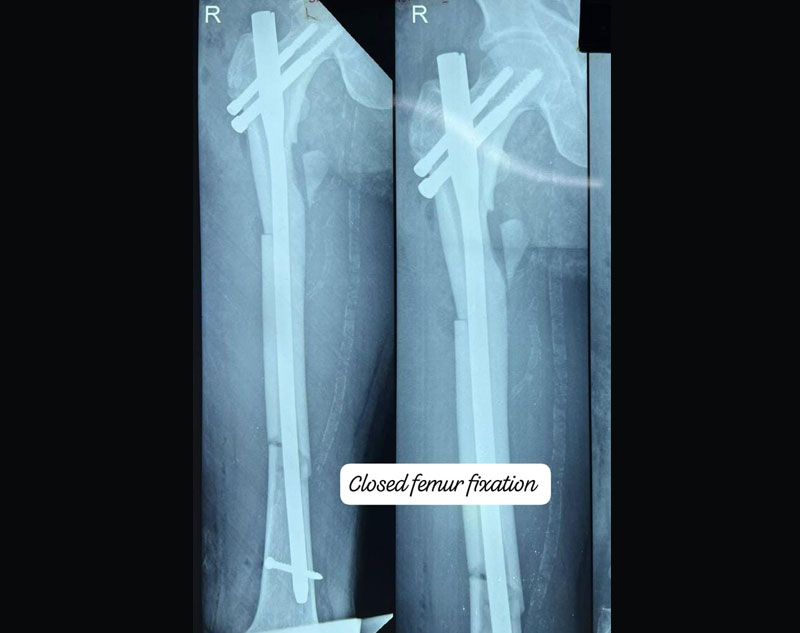

Complex Trauma in orthopedics refers to severe injuries involving multiple or complicated fractures, often combined with soft tissue damage.

These injuries may involve:

Treatment for complex trauma requires a multidisciplinary approach, including surgical intervention, internal/external fixation, and sometimes reconstruction of damaged tissues.